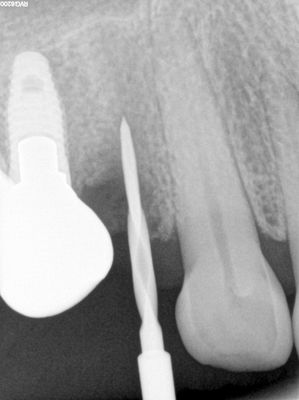

relatively straight forward immediate placement, loss of labial plate at apex of 3mm, implant placed well away from that site, grafted that region from internal of socket with membrane and bone prior to placing implant. additional bone placed post implant placement .